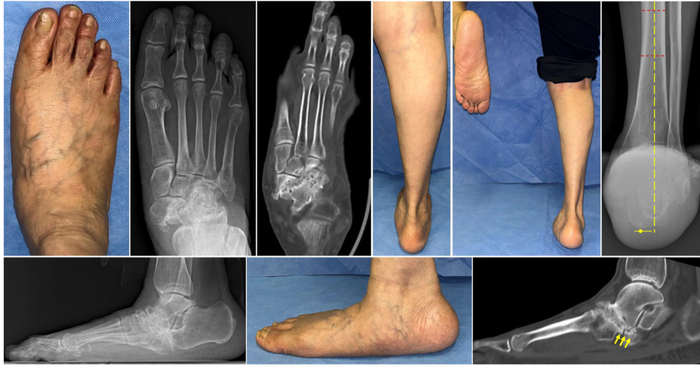

Сегодня разберем ревизионный случай hallux valgus. И остановлюсь конкретно на малых пальцах (о ревизии первого луча опишу как-нибудь другой раз).

Имеет подобную стопу (ранее была выполнена реконструкция в объёме scarf и akin). По результатам получен рецидив деформации.

Видим характерные проблемы: наличие гиперкератозов под головками малых лучей (это свидетельствует о наличии избыточной нагрузки) и девственно чистую кожу под головкой первой плюсневой кости (значит нагрузка на первом луче отсутствует, что является катастрофой для стопы).

После реконструкции первого луча (в данном случае была выполнена остеотомия Austin, потому что позволяло состояние кости) мы получаем наличие деформации малых пальцев во фронтальной плоскости.

Интраоперационная оценка положения пальцев стопы. Видно нарушение нормального положения пальцев.